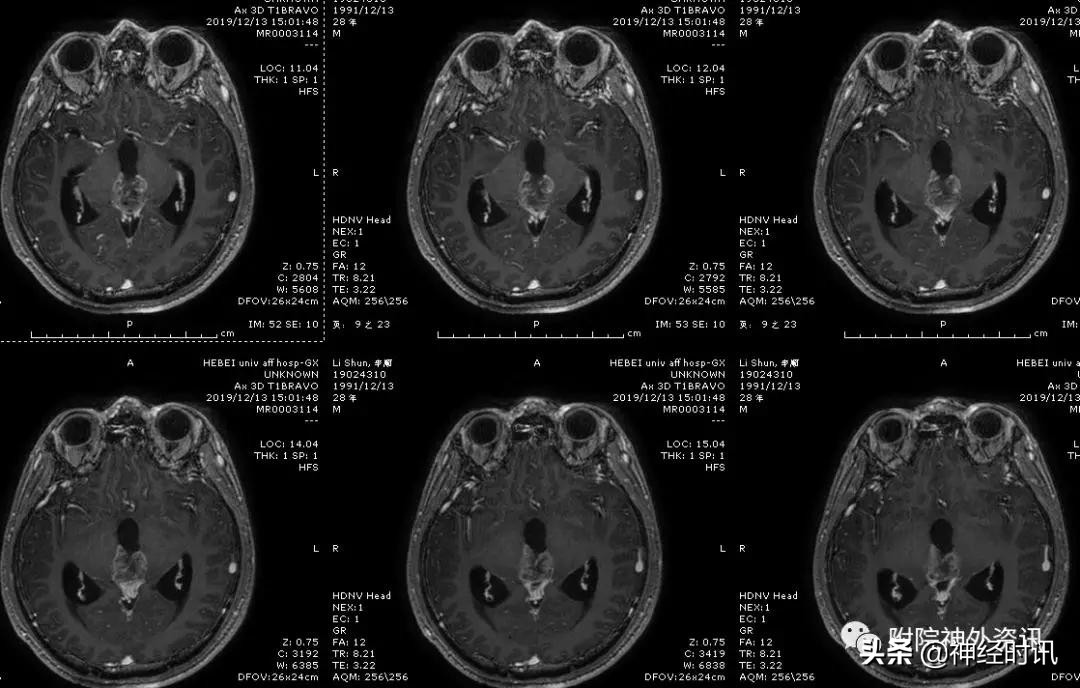

男性,28岁,主因复视20余天入院,查体双瞳孔不等大,直径左=3. 5mm,右=3.0 mm,对光反射迟钝,双眼上视困难,左眼眼位异常,向内下斜视。